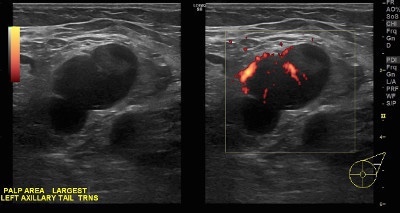

👉Reactive nodes can be difficult to distinguish from metastatic nodes (Image).

👉In general, benign causes of nodal enlargement tend to thicken the cortex diffusely.

👉In addition, it is not uncommon to have a metastatic node adjacent to a normal node, but all nodes in a region tend to be reactive when the cause is benign.

👉Finally, a reactive node has blood supply on Doppler examination through a single hilum, whereas metastatic nodes tend to have multiple transcapsular vessels (Image).